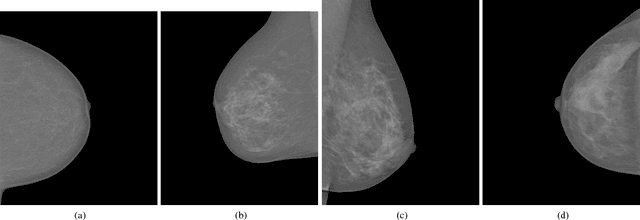

Abstract:Mammographic breast density, a parameter used to describe the proportion of breast tissue fibrosis, is widely adopted as an evaluation characteristic of the likelihood of breast cancer incidence. In this study, we present a radiomics approach based on residual learning for the classification of mammographic breast densities. Our method possesses several encouraging properties such as being almost fully automatic, possessing big model capacity and flexibility. It can obtain outstanding classification results without the necessity of result compensation using mammographs taken from different views. The proposed method was instantiated with the INbreast dataset and classification accuracies of 92.6% and 96.8% were obtained for the four BI-RADS (Breast Imaging and Reporting Data System) category task and the two BI-RADS category task,respectively. The superior performances achieved compared to the existing state-of-the-art methods along with its encouraging properties indicate that our method has a great potential to be applied as a computer-aided diagnosis tool.